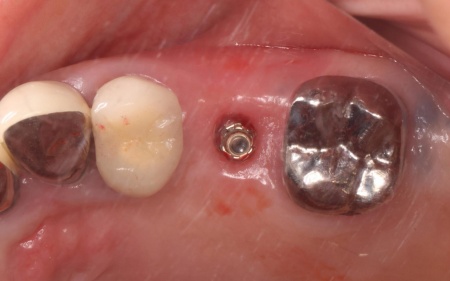

治療前

治療中

治療後